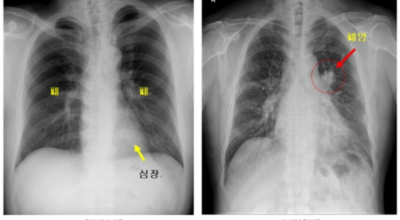

폐암은 폐에 생기는 악성 종양을 말합니다. 폐에서 직접 발생하는 원발성 폐암과, 다른 장기에서 전이되어 온 전이성 폐암으로 나눌 수 있어요. 전 세계적으로 매년 약 130만 명이 폐암으로 사망하는데, 이는 암으로 인한 사망 원인 중 가장 높은 비중을 차지하고 있습니다.

폐암 초기 증상으로는 혈담이 있습니다. 혈담은 쉽게 말해 가래에 피가 섞여 나오는 경우를 뜻합니다. 폐암이 폐 중앙부 기관지 근처에 위치할 경우 나타나는 혈담은 폐암 환자의 25% 이상이 경험하는 증상입니다. 만약 기침할 때 심한 가래나 혈담이 섞여 나온다면 즉시 병원을 방문하시길 권합니다.